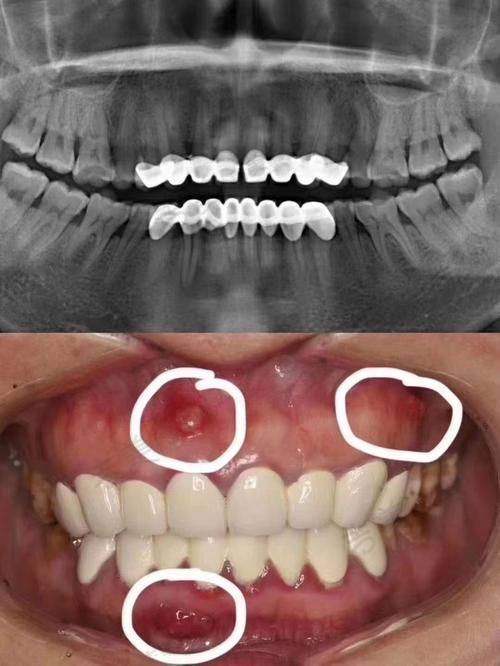

烟台德韩万达院口腔门诊部拥有众多特色项目。即刻种植牙是其一大亮点,该技术能够在拔牙后立即植入种植体,大大缩短了治疗周期,减少了患者的痛苦。美国3种种植体和瑞士ITI种植体,为患者提供了更多的选择,这些种植体具有良好的生物相容性和稳定性,能够确保种植成效。氟斑牙治疗采用精良的技术和方法,有效改善牙齿外观和色泽。儿童龋齿治疗针对儿童牙齿特点,采用温和、微痛的治疗方式,让孩子轻松摆脱龋齿困扰。地包天矫正项目,医生会根据患者的具体情况制定个性化的矫正方案,帮助患者修复正常的咬合关系。洗牙项目采用精良的设备和技术,能够有效清除牙齿表面的污垢和菌斑,预防口腔疾病。口腔预防保健则注重从源头预防口腔问题,为患者提供专精的口腔卫生指导和建议。拔牙、牙套、活动义齿、牙齿美白等项目也都有着专精的医生团队和精良的技术设备支持,能够为患者提供优质的诊疗服务,充分体现了烟台德韩万达院口腔门诊部的实力。